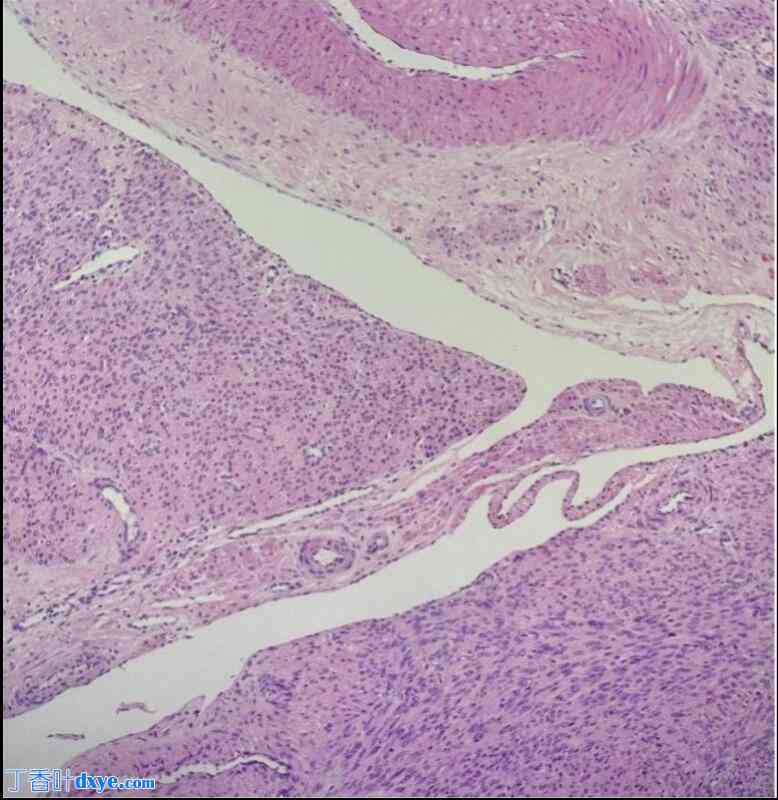

患者在全身麻醉下接受宫腔镜检查。发现八个黏膜下肌瘤,大小从 2 到 4 厘米不等,位于子宫前壁、后壁和侧壁。宫颈管外观正常。使用 Myosure XL 刮除器(Hologic Inc.,美国马萨诸塞州马尔伯勒)完整切除七个肌瘤,并使用 Gynecare 双极电切镜(Ethicon Inc.,美国新泽西州萨默维尔)切除一个深部 FIGO 1 型肌瘤(图 2)。

图 2.

宫腔镜视图显示四个带星号的黏膜下子宫肌瘤。